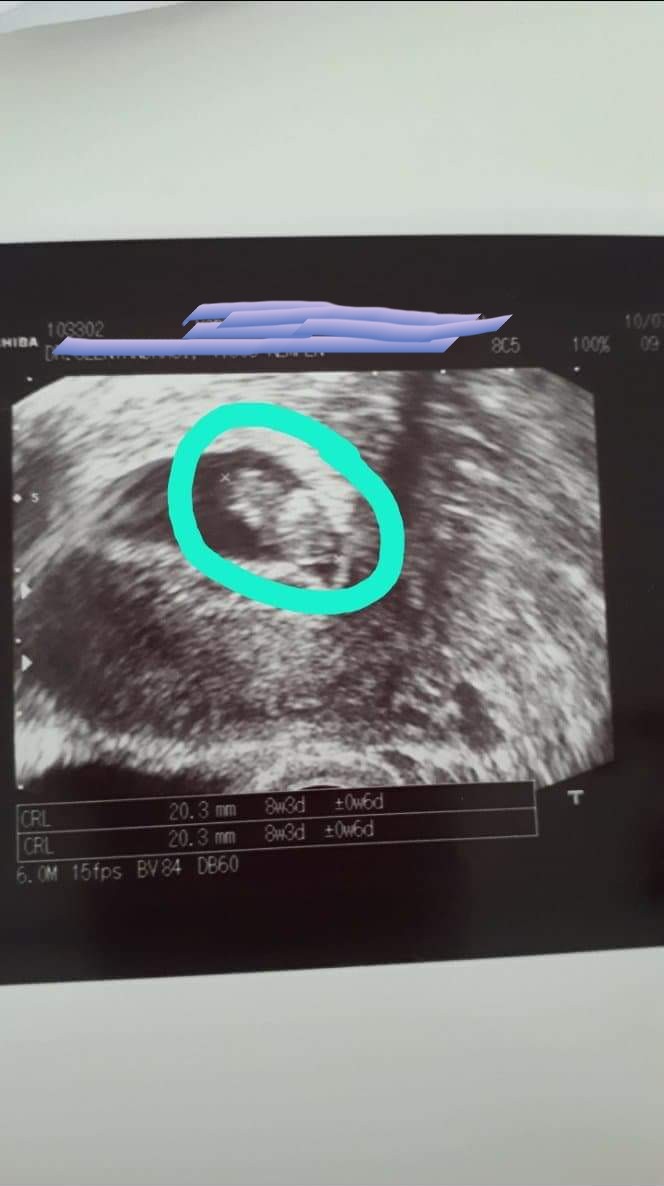

Hej my też dziś po wizycie u nowego lekarza wszystko ok dziecko o tydzień mlodsze, byłam na usg z córką i mężem wyszli zaczęłam się ubierać i zemdlalam postawiłam wszystkich na nogi niewiem ale chyba za dużo wrażeń, strasznie się bałam. Potem chcieli krew pobrać to dwie ręce poklute A krwi brak nigdy tak nie mialam 40min 2 fiolki do minimum. Potem już nawet bez kropli.za 2 tyg muszą znów bo za mało.a oto nasze baby